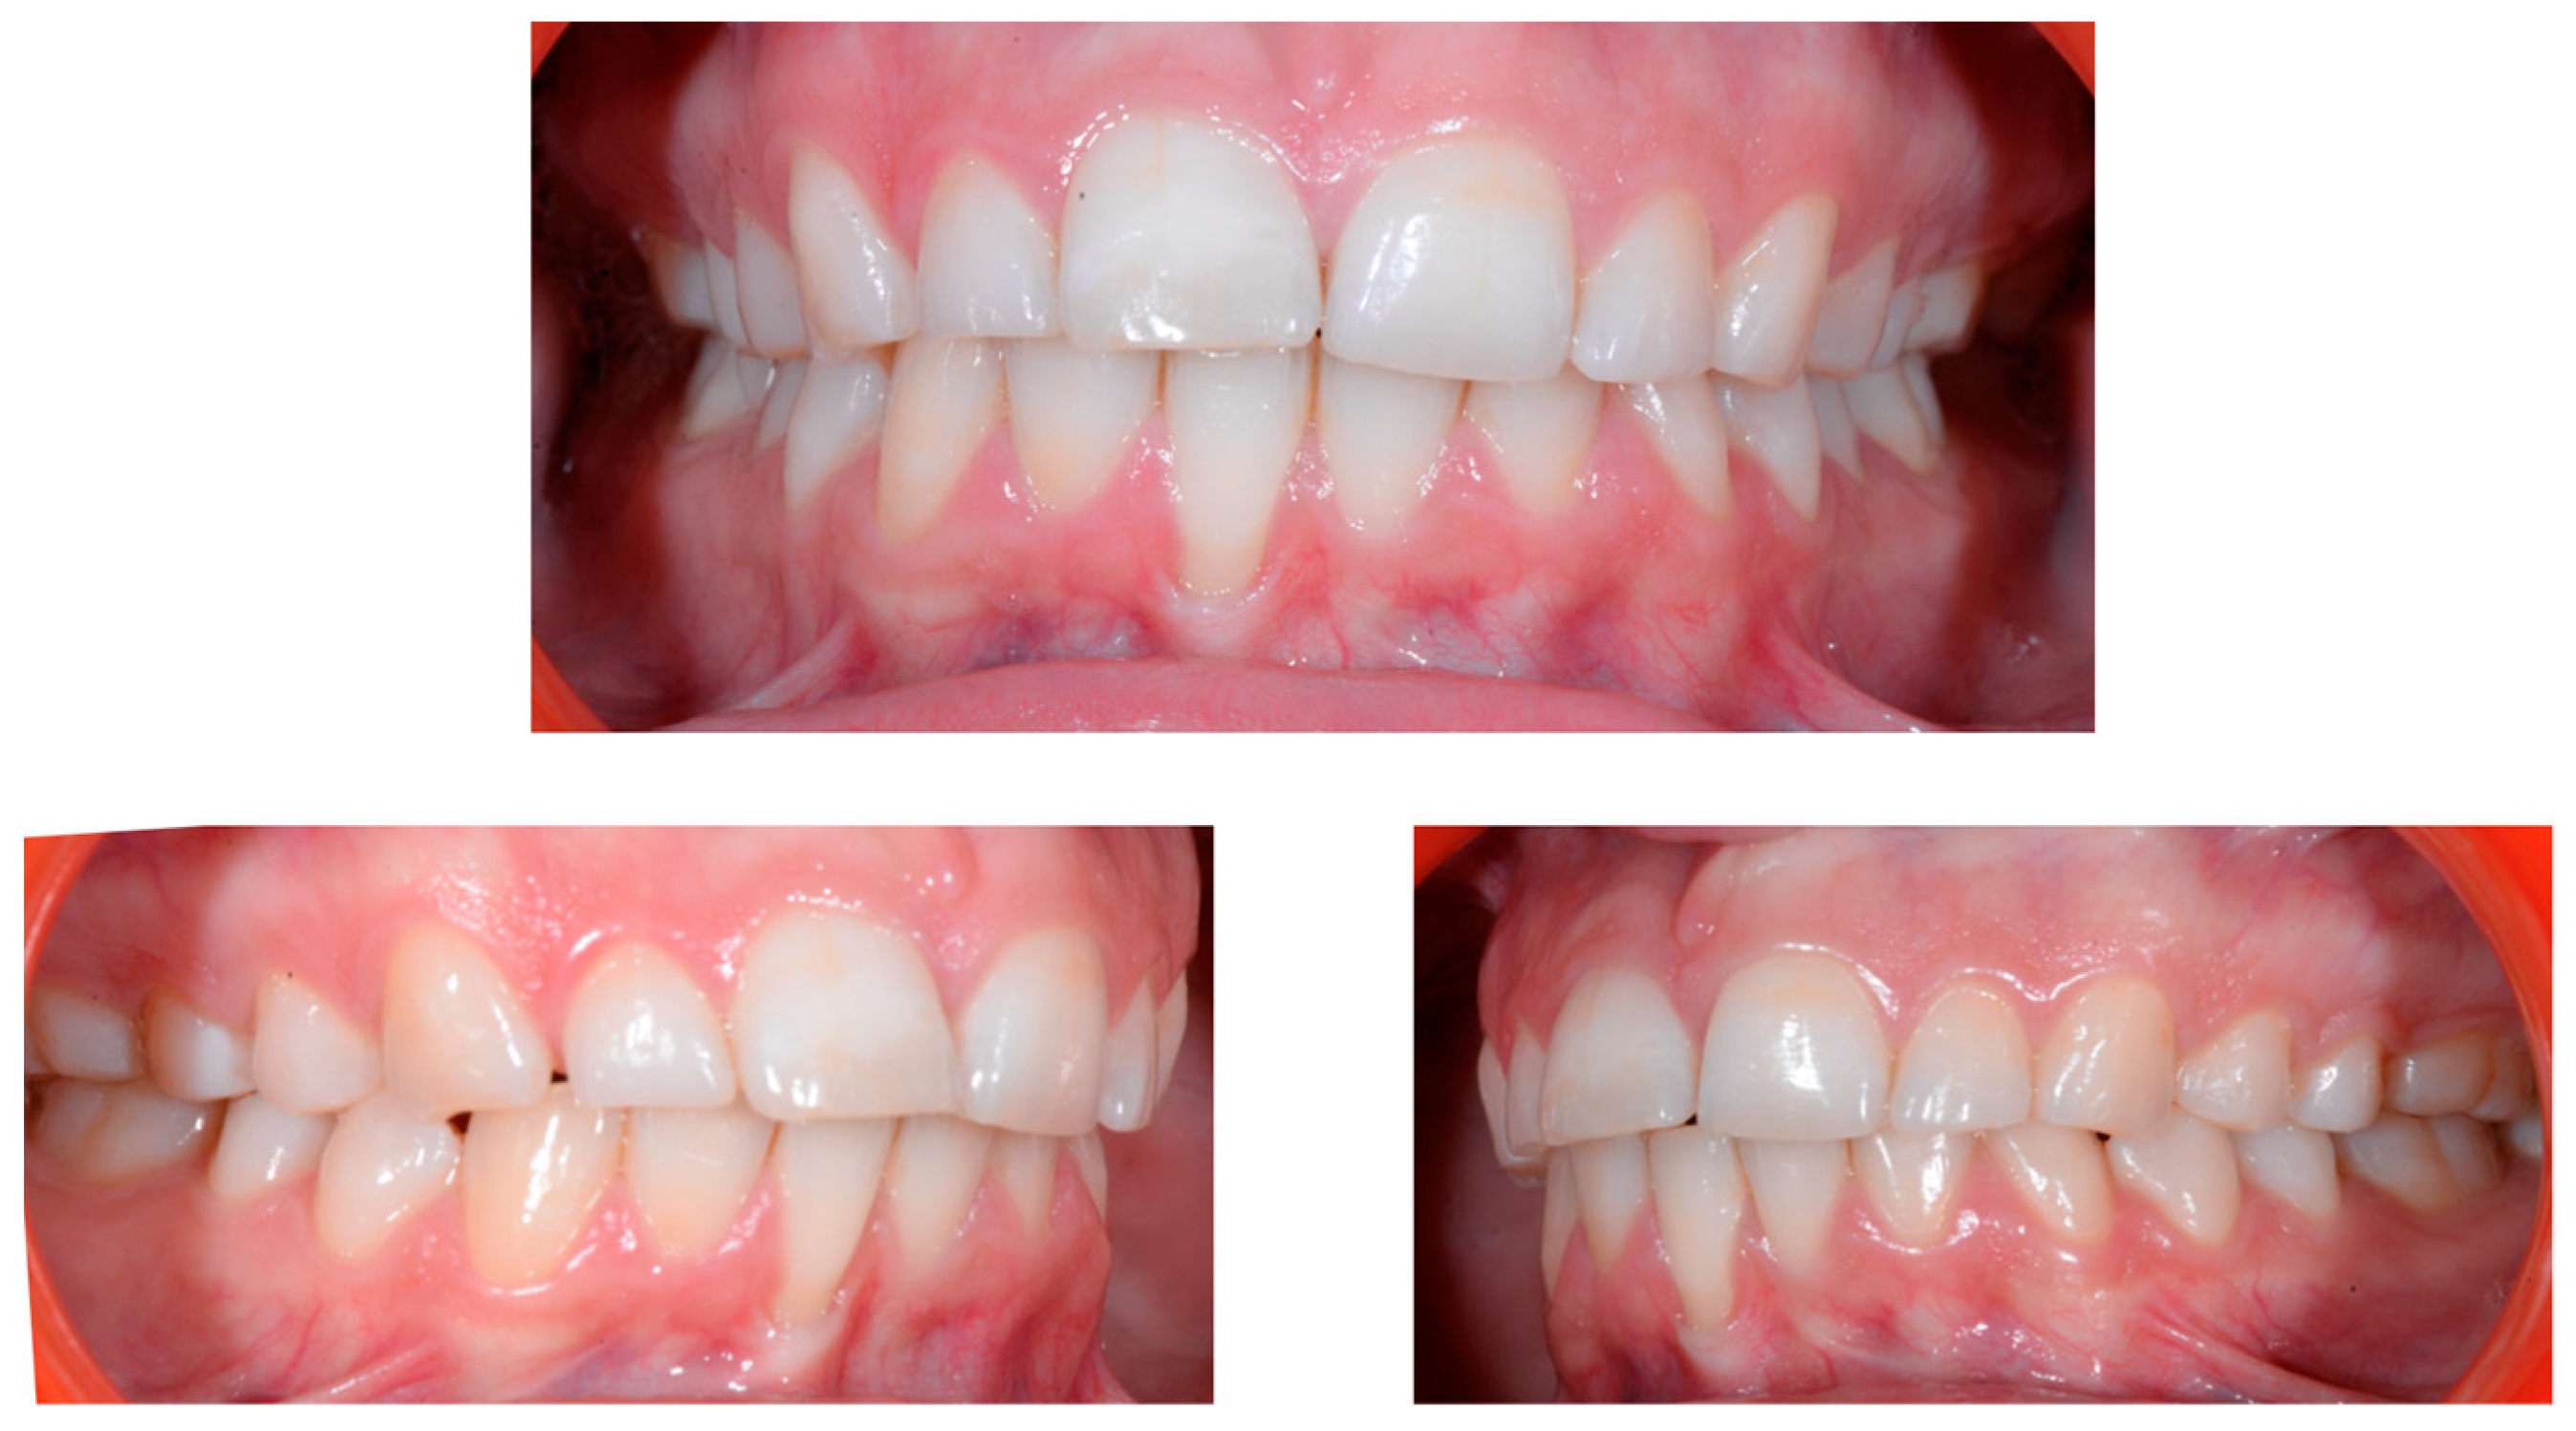

A 22-year-old female patient in good health had a consultation because she was concerned about the “root prominence” of tooth 41. She wore a mandibular retainer wire when she was 16 years old at the end of her orthodontic treatment. She has good oral hygiene, despite the presence of tartar between 31 and 41, and a right and left Class I with a slight deviation of the midlines (Figure 1).

Early wire syndrome. Frontal and lateral views.

In Figure 2, the following can be observed: a difference in gingival margin height between 41 and 31, a difference in height of the incisal edges of 41 compared to the adjacent teeth, and the onset of gingival recession on 41 associated with the visibility of a vestibular arch corresponding to its root.

Early wire syndrome. Frontal views.

In the lateral view (Figure 3), the prominence of the root of 41 was confirmed.

Early wire syndrome. Lateral view.

Occlusal views (Figure 4) confirmed the presence of a mandibular retainer which appears intact, without fracture or debonding, along its entire length. In addition, the vestibular surface of 41 appeared to have a difference in visibility from the adjacent teeth. Based on these clinical findings, wire syndrome starting on tooth 41, called the “X-effect” type, was suspected.